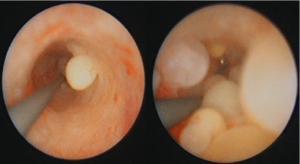

What caused this finding on cystoscopy?

Chronic inflammation of the ureter

(Cysts in the ureter = urethritis cystica)